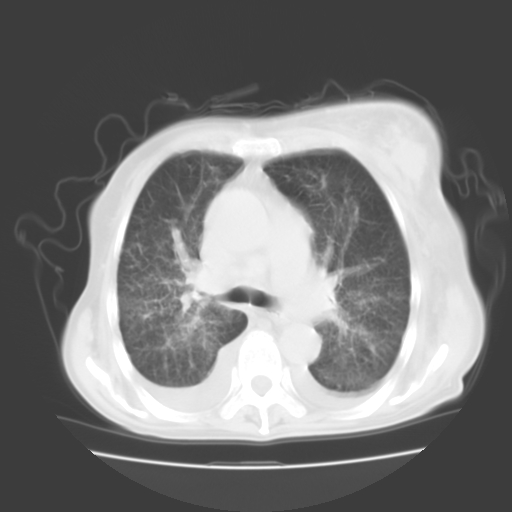

女70y乳腺ca(针吸活检)

多部位转移瘤的诊断可以肯定,我的疑问是:双肺对称高密度影及胸水是否为心衰肺水肿,病人体虚弱,不好意思图象传的乱![em9]

肺部病变为淋巴转移,肝脏转移,及局部淋巴转移。胸水可能为淋巴回流受阻(血性的考虑胸膜转移)

1)左侧乳腺癌并左侧腋窝及纵隔淋巴结转移,两肺淋巴道转移(癌性淋巴管炎),肝脏多发性转移。2)双侧胸腔积液。3)慢性胆囊炎。

1)左侧乳腺癌并左侧腋窝及纵隔淋巴结转移,肝脏多发性转移。2)双侧胸腔积液伴双肺蝶翼样磨玻璃高密度影,双侧肺门血管影增粗(图像不全,肺门层面没纵隔窗),考虑心功能不全所致。3)慢性胆囊炎伴壁钙化。